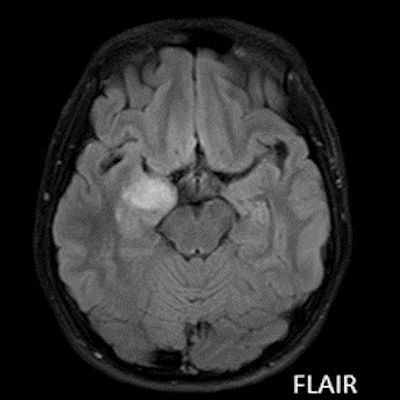

- A) Sağ temporal lob anteromedialinde silik sınırlı BT’de hipodens (ok), MRG’de T2AG ve FLAIR hiperintens (oklar), T1AG izo-hipointens (ok) sinyal özelliğinde ekspansil kitlesel lezyon izlenmektedir.

- MRG: T1A serilerde solid komponent izo-hipointens, T2A serilerde genellikle hiperintens sinyalde görülür. Peritümöral T2/FLAIR hiperintens kitle ödemi oldukça nadirdir. T1 C+ görüntülerde solid komponentte değişken oranda kontrastlanma ,T2*(SWI) serilerde eğer kalsifikasyon eşlik etmekteyse buna bağlı blooming artefaktları görülebilir.